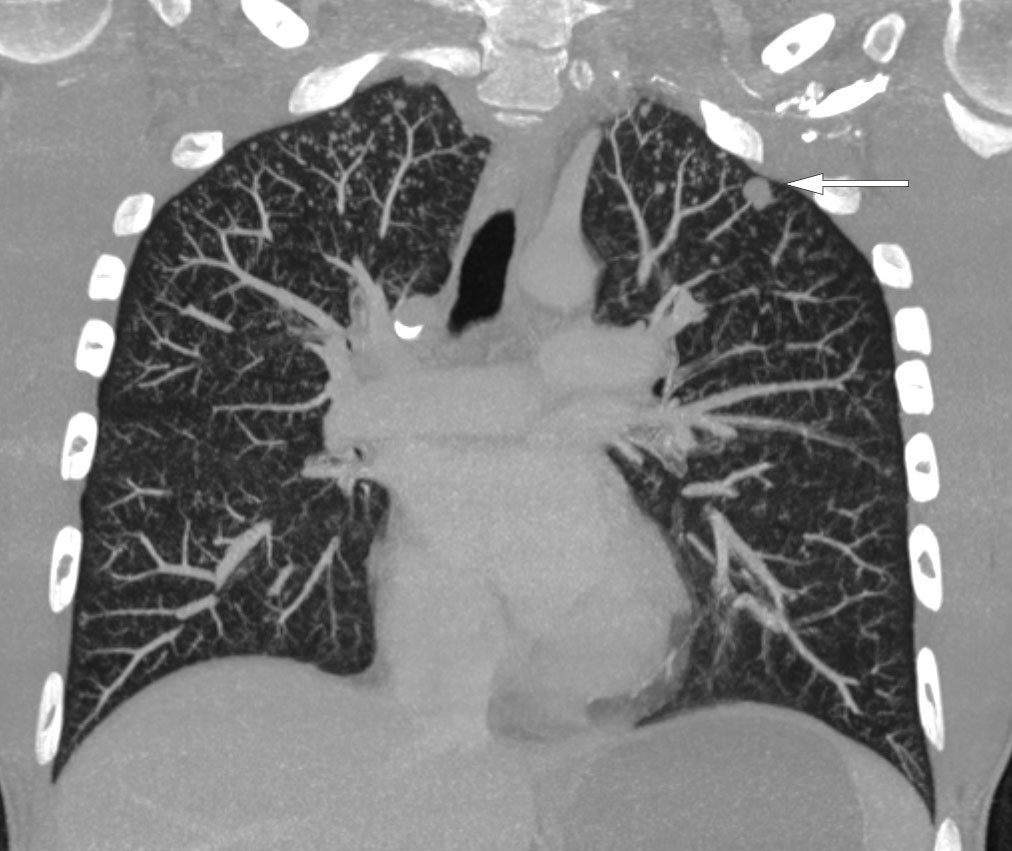

CT-undersøkelse uten kontrast av hodet ble tatt umiddelbart etter innleggelse og viste lavattenuerende forandringer i hvit substans frontalt i høyre storhjernehemisfære (fig 1) og i høyre lillehjernehemisfære. Supplerende magnetisk resonanstomografi av hjerne og medulla påfølgende dag avdekket multiple lesjoner i hjernestamme, lillehjerne og begge storhjernehemisfærer (fig 2). Nevroradiolog vurderte funn som forenlig med multiple metastaser, hjernetuberkulose, parasittsykdom eller septiske embolier med sekundær abscessdanninger. Spinalvæskeundersøkelse viste leukocyttnivå på 9 · 109/l, men ellers normale verdier for erytrocytter, glukose og protein. Det ble samme kveld utført CT av thorax, abdomen og bekken for å se etter tegn til ekstracerebral sykdom, inkludert kreft, bakterielt infeksjonsfokus, tuberkulose i eller utenfor lunger, eventuelt tegn til parasittsykdom. Denne avdekket multiple mikronoduli i lungene, mest i apikale deler av begge overlappene, én litt større nodulus apikalt og lateralt i venstre overlapp samt en liten høyattenuerende lesjon til høyre for avgangen av høyre hovedbronkus som var forenlig med en forkalket lymfeknute (fig 3). Det var multiple lavattenuerende lesjoner i abdomen og bekken, mest i øvre del av lever, og i tillegg lesjoner i nyre og prostata. Radiologen beskrev funnene som mest forenlig med miliær tuberkulose.

Tuberkulosebakterier overføres via luftsmitte. Dersom kroppens immunforsvar ikke bekjemper infeksjonen, vil det i lungene dannes et granulom eller en tuberkel gjennom en inflammatorisk prosess. Dette kalles et primærfokus. Et primærfokus med tilhørende tuberkuloseinfiserte hilusglandler danner et primærkompleks. Herfra kan bakteriene spres via blodbanen. I de fleste tilfeller vil immunforsvaret hindre videre spredning, men bakteriene kan også overleve i lang tid. Tilstanden kalles da latent tuberkulose, noe som per definisjon ikke gir symptomer. Hos ellers immunfriske pasienter vil 90–95 % av de som blir infisert kun få latent tuberkulose, mens 5–10 % utvikler aktiv sykdom. Blant de med aktiv sykdom vil de fleste utvikle lungetuberkulose, men rundt en firedel til en tredel vil få ekstrapulmonal tuberkulose. Ved disseminert eller miliær tuberkulose kan infeksjonen spres via blodbanen til alle deler av kroppen. Vår pasient hadde lesjoner i sentralnervesystemet, lunger, lever, nyrer og prostata som kunne passe med hematogen spredning av tuberkulose.